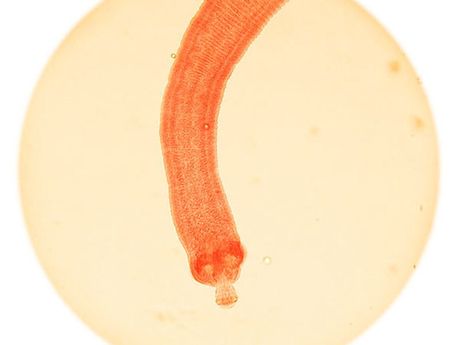

10. Giun sán: 700 ca tử vong/năm

Nói tới kí sinh trùng, giun sán là nguyên nhân gây sán gạo, một loại nhiễm trùng giết hại tới 700 người mỗi năm.

8. Giun đũa: 4.500 cái chết mỗi năm

Giun

đũa gây ra cái chết cho 4.500 người hàng năm, theo một nghiên cứu năm

2013. WHO cho biết sự nhiễm giun bắt đầu trong ruột non, căn bệnh giun

đũa ảnh hưởng tới trẻ em nhiều hơn người lớn.